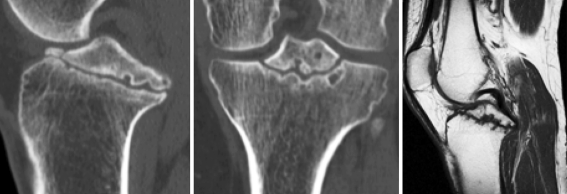

Magnetic resonance imaging and computed tomography showed pseudo-arthrosis of a large bony avulsion of the tibial attachment of the PCL extending to both the medial and lateral tibial plateau The magnetic resonance imaging also showed an intact PCL and did not reveal any signs of concomitant intra-articular injuries of the knee (Fig. 2). Bone scintigraphy demonstrated increased activity at the proximal left tibia.

Fig. 2.

Computed tomography revealing a large bony avulsion of the tibial attachment of the PCL. Magnetic resonance imaging shows an intact PCL